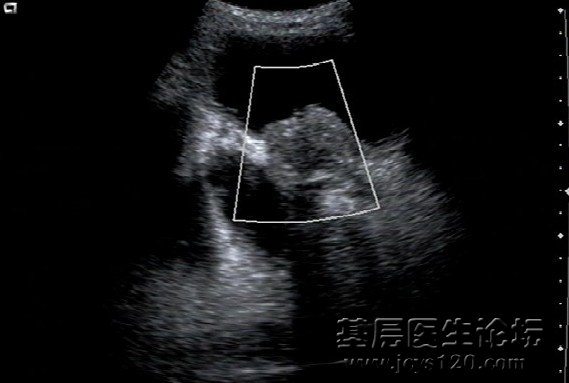

一患者 男 85岁,因前列腺增生 超声发现,检查所见:膀胱形态轮廓正常,在膀胱壁右侧壁可见一个大小约81x58mm的异常回声,形状呈椭圆形,壁薄光滑,内呈一致性暗区,与膀胱相通,排尿后此异常暗区缩小。 阅读全文>

三天前一好朋友来诊,说脖子肿,做吞咽后,诊断甲状腺肿大,今天做彩超,诊断甲状腺混合型占位,请教各位老师‘混合型’什么概念肿瘤恶性的吗? 阅读全文>